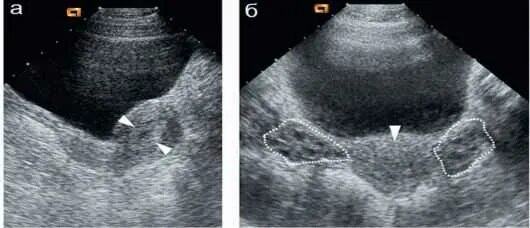

Трансабдоминальное узи